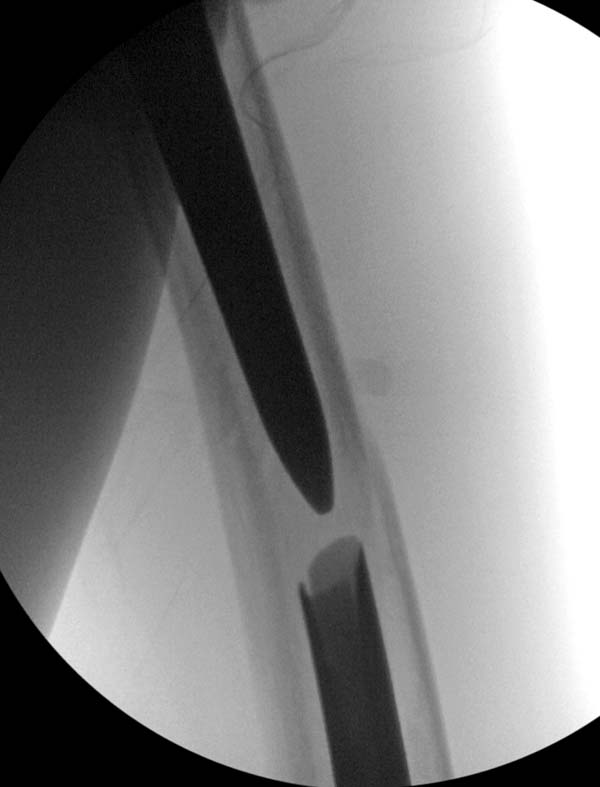

Операция не обошлась без казуса, при подготовке гвоздя произошла ошибка

в расчете. Пришлось коррегигировать по ходу операции, где длинный

дистальный отдел гвоздя срезали во время операции.

А так вроде первый американский опыт прошел удачно. У больного низкий

гемоглобин, который подправили во время операции переливанием крови.

надеюсь, контрагированные мышцы сохранит длину конечности. Контрольный

снимок показал устойчивую фиксацию.